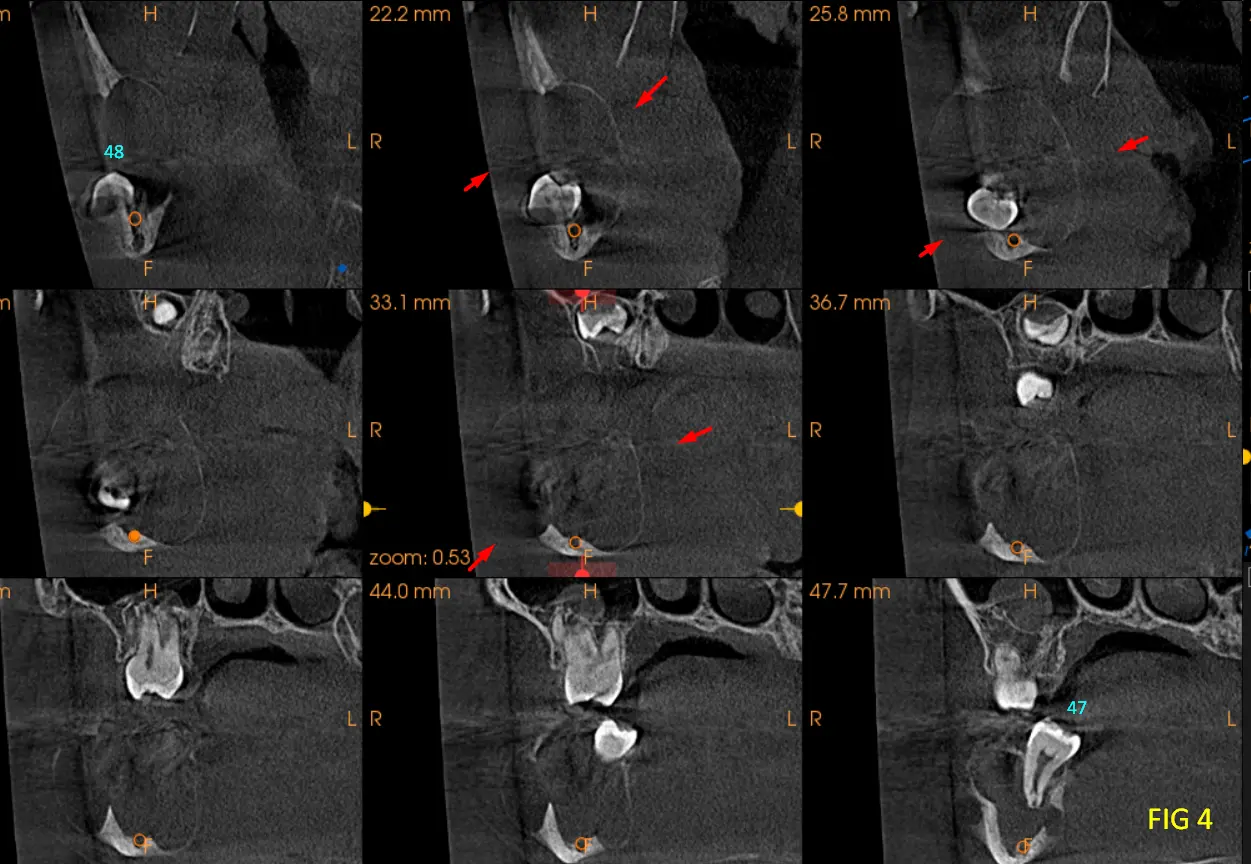

En las reconstrucciones 3D y cortes multiplanares (ver Fig 1, 2 y 3) se observa lesión hipodensa, unilocular, ubicado en rama mandibular, expandiéndose desde la rama ascendente mandibular hasta el ángulo y parte posterior del cuerpo mandibular, su contenido es homogéneo, involucra al germen de la pieza dentaria 48. Desplaza el conducto hasta la basilar, expande tabla lingual y vestibular.

En cortes coronales (Fig. 4) se aprecia los bordes definidos y parcialmente corticalizados que trata de delimitar la lesion, los cuales se encuentran sumamente adelgazados, como así también el desplazamiento de la hacia lingual pieza dentaria 47, y el desplazamiento de la pd 48 hacia la basal y hacia vestibular, los signos tomográficos nos llegavan a un diagnóstico presuntivo de Ameloblastoma Uniquístico. Se recomienda al profecional un estudio de Biopsia para tener un diagnóstico de certeza.